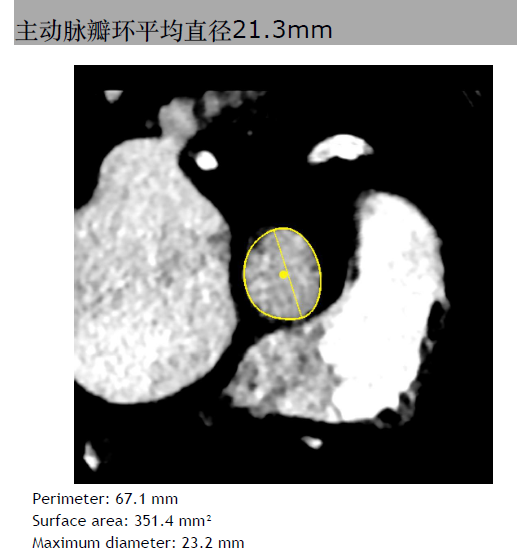

三叶瓣,主动脉瓣环平均直径21.3mm。右冠脉高度10.3mm,右窦直径:28.4mm。左冠脉高度14.1mm,左窦直径:30.4mm。STJ平均直径25.4mm,高度17mm。